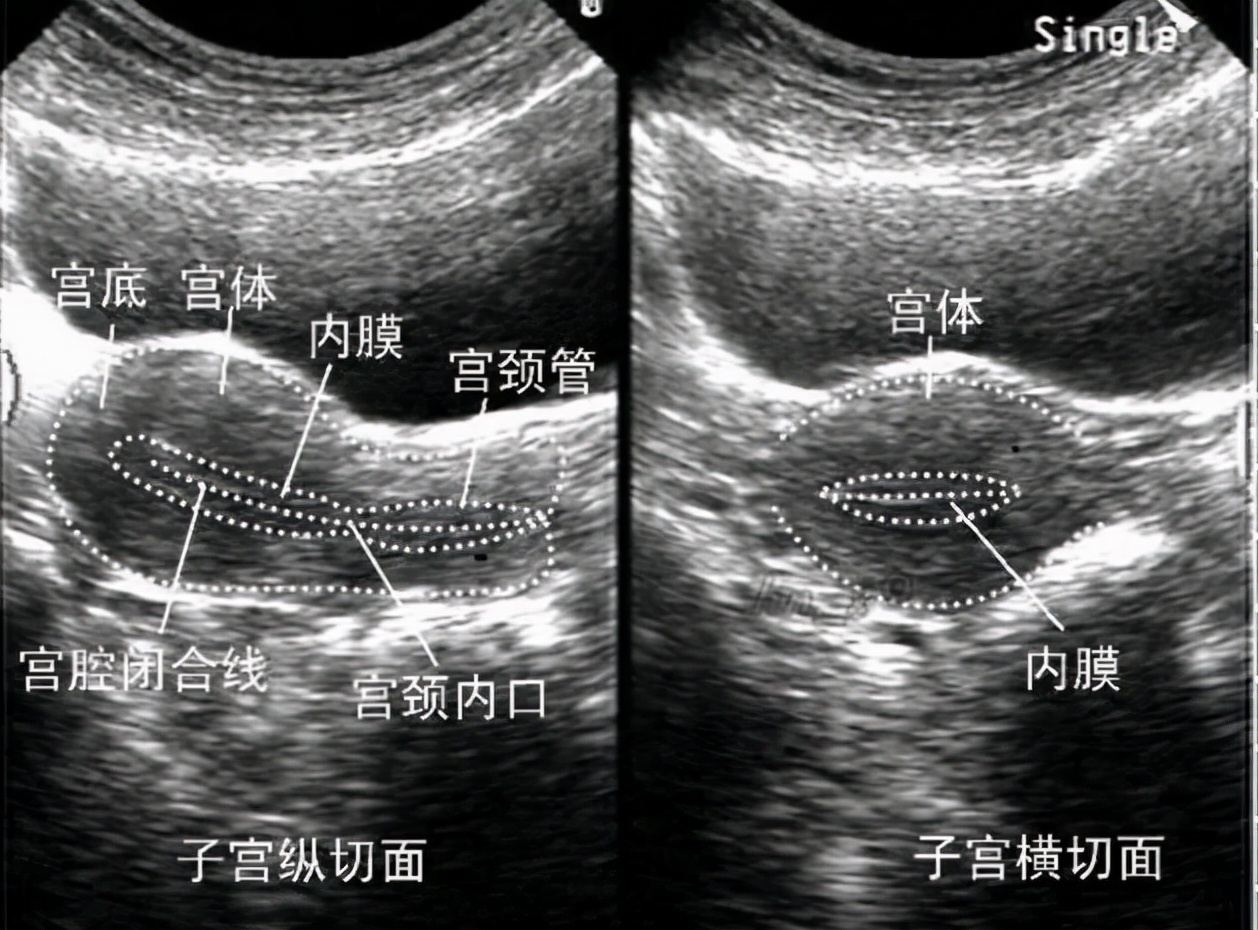

大家都知道,子宫内膜厚度在8mm到12mm是最适宜受精卵着床的。一般来说,子宫内膜厚度小于7mm,就会诊断为子宫内膜薄。如果试管移植周期,患者子宫内膜<7mm,建议取消周期。有研究表明,如果子宫内膜厚度小于6mm,怀孕成功率显著下降。